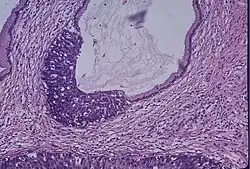

Breast cancer is the most common cancer for women.[23] Screening is done to detect the disease early in asymptomatic women, in an attempt to achieve an earlier diagnosis and lower mortality. Different screening tests are used for breast cancer screening, including clinical and self-examination of the breasts, mammography, and magnetic resonance imaging (MRI). Mammography is the standard method for breast cancer screening. This method is reported to give a 40% reduction in the risk of dying from the disease.[24] Breasts with less fat and more fibrous tissue are known as dense breasts, they are a risk factor for breast cancer. The tissue makes it harder to find tumors while doing a mammogram, therefore MRI screening is proposed to supplement the mammogram in these patients.[24]